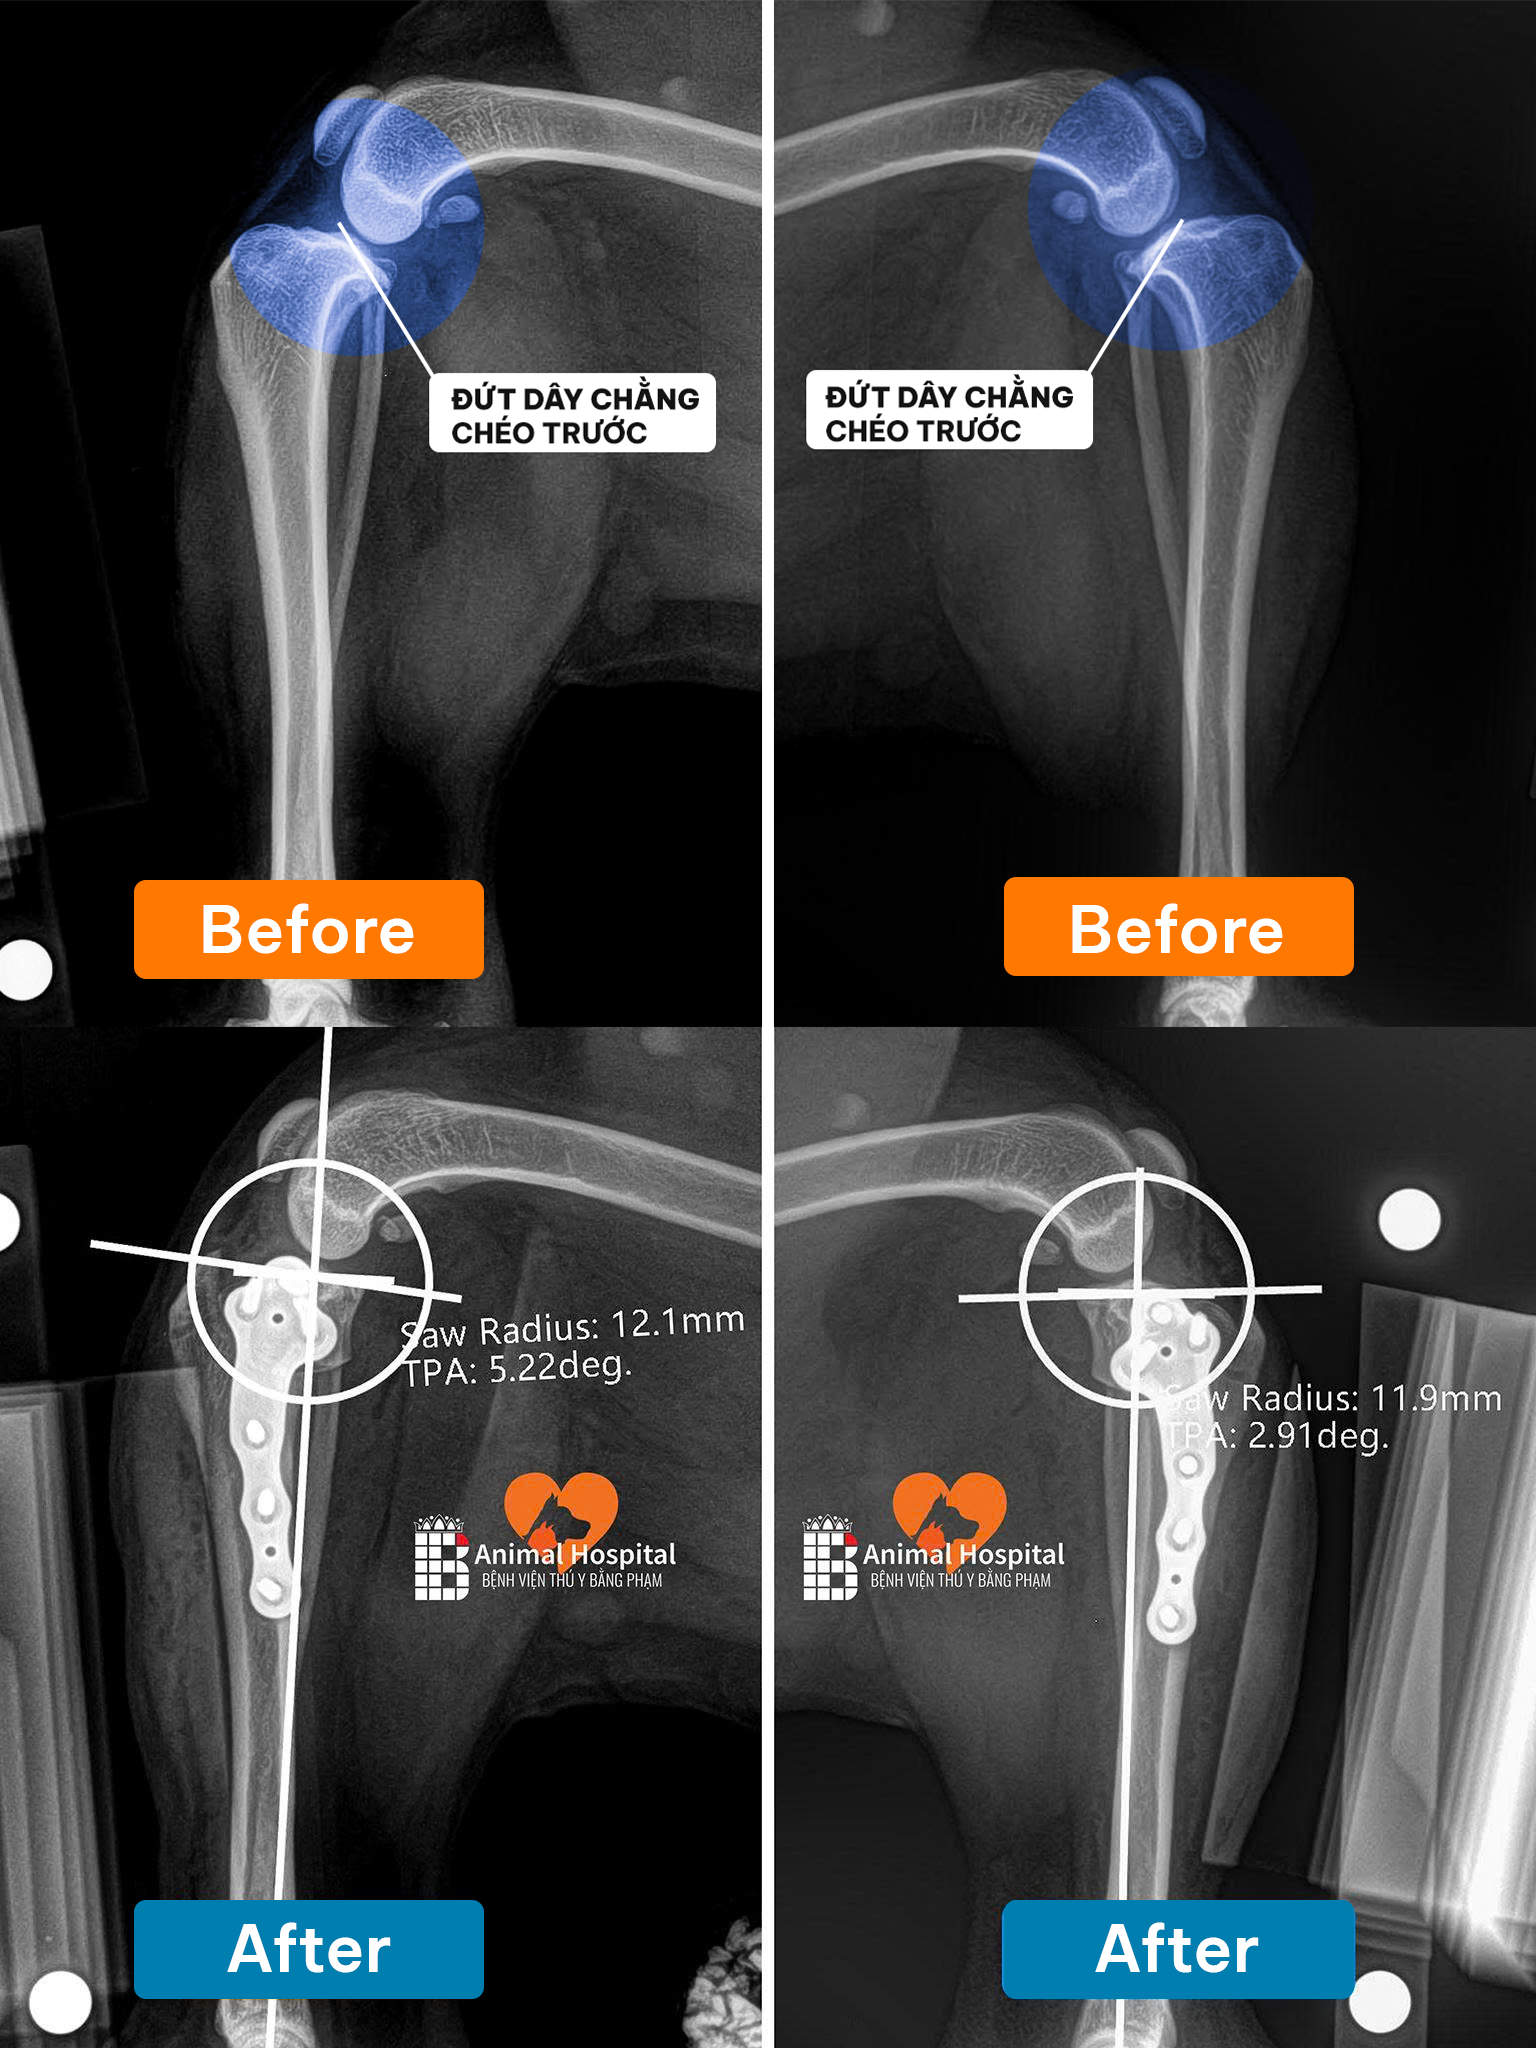

🔧 Giải pháp phẫu thuật | Total Hip Replacement (THR)

Sau khi đánh giá tổng thể tình trạng thoái hóa khớp háng ở chó, team bác sĩ tại Bệnh Viện Thú Y Bằng Phạm đã quyết định thực hiện thay khớp háng toàn phần bằng hệ thống tiên tiến 𝐁𝐥𝐮𝐞𝐒𝐀𝐎 𝐁𝐢𝐨𝐧𝐢𝐜 𝐇𝐢𝐩 – một trong những công nghệ hàng đầu hiện nay trong lĩnh vực cấy ghép khớp ở thú y.

📸 Kết quả sau phẫu thuật thái hóa khớp háng ở chó | Post-op Results

Ảnh X-quang hậu phẫu cho thấy:

- Implant được đặt đúng vị trí

- Trục khớp chuẩn xác

- Tiếp xúc xương tốt – là tiền đề lý tưởng cho sự phục hồi.